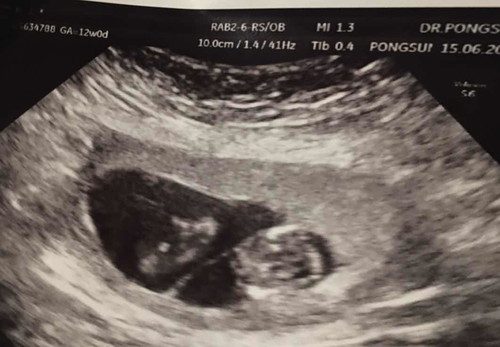

ท้องแฝดค่ะคนล่ะถุงคนน้องกับคนพี่ห่างกัน8วันคนพี่12วีค+1คนน้อง11วีค

ห่างกันเพิ่มคนขึ้นทุกๆๆ2วีคอยากทราบแม่ท่านไหนมีประสมการณ์แบบนี้ไหมค่ะเป็นห่วงคนเล็กหมอบอกเขาได้รับสารอาหารไม่เท่าคนพี่❤️❤️❤️❤️